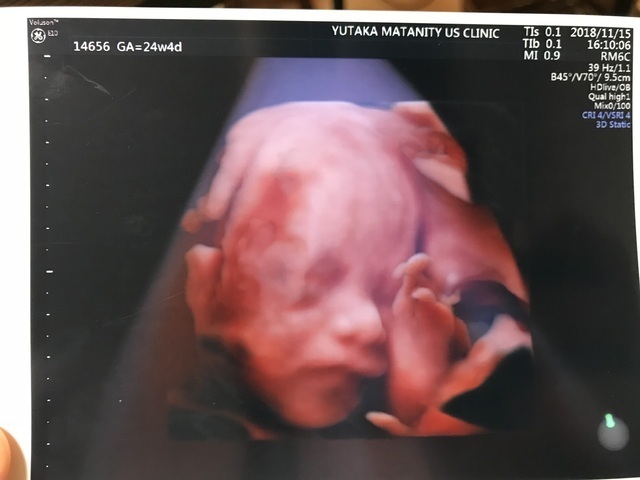

24週4日(24w4d・女の子)|★☆★ さん(30歳)

エコー写真撮影時のエピソード:

なかなか男の子か女の子かはっきりしなかったけど、この日はおまたのエコーできっと女の子だろうと初めてわかった時でした。どちらでも良いかなと思っていたけど性別がわかったらまた生まれてくる楽しみが倍増してとてもうれしかったのを覚えています。

その頃は便秘に苦しみ切迫傾向だと言うことで心配にもなり気持ちが変動しがちでした。